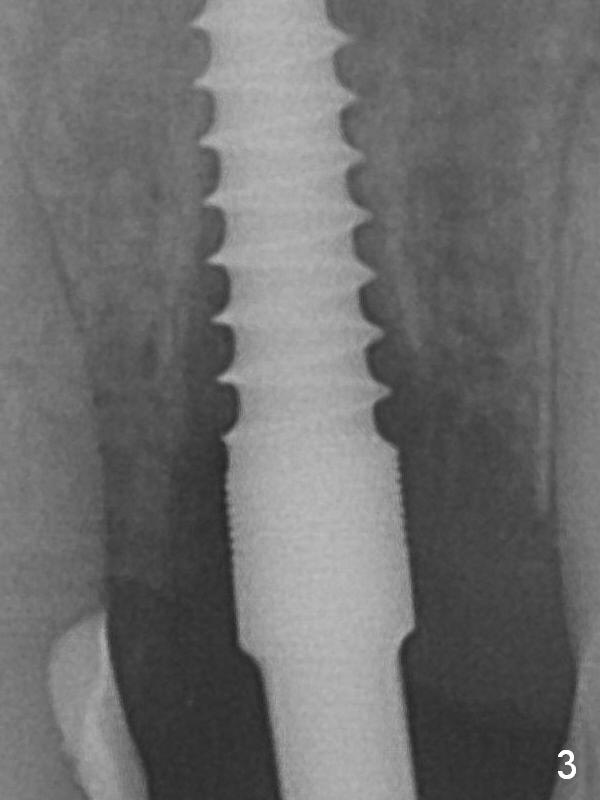

The peri-implant space (Fig.3) is filled with bone graft (Fig.4 *). The apical portion of the socket appears to have reduced 4 months postop (Fig.14). When the patient returns 1.5 years post cementation, there is increased bone density next to the coronal portion of the implant, equivalent to the bone graft (Fig.15 *). The crestal bone loss remains 2.5 years post cementation (Fig.17 *), although there is no sign of periimplantitis. Oral hygiene is poor.